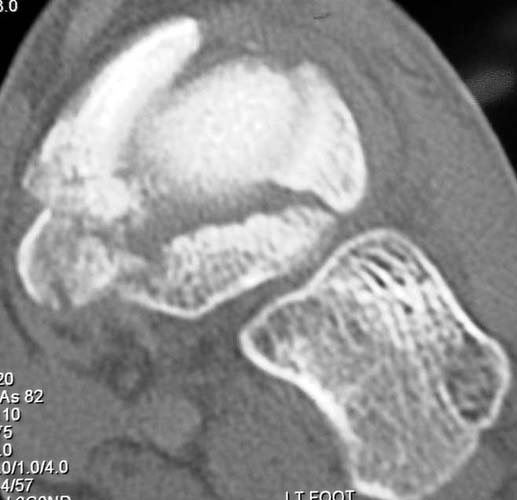

39yo male construction worker presents with 10 day old closed comminuted navicular # following low velocity fall from small motorcross bike.